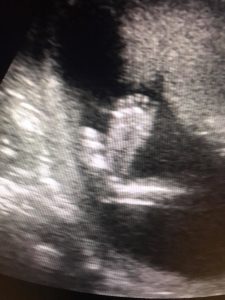

At five weeks gestation, Victor and I were so excited and happy to find out we were expecting a new little one to add to our small family. My job offers a first-trimester screen where they do an ultrasound and blood work to check for common chromosomal abnormalities like Trisomy 18 and 21. We had no histories of these conditions, and I didn’t think our baby had it, but I did the first-trimester screen just so I could see my baby during the ultrasound. It was such a thrill to see my little one moving inside of me, kicking and punching away.

Ultrasound of Angel from Live Action on Vimeo.

I saw my baby again at 15 weeks and received the same diagnosis along with the news that it’s a girl — the little girl we hoped for, the little girl who we dreamed of raising next to our little guy. She seemed so perfect. I could see that her head wasn’t like other babies’ heads that I had seen in ultrasounds or like my own son’s when he was in the womb. It didn’t matter to me, she was my little princess.